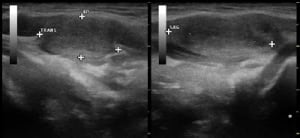

U.a. weisen Gewichtsveränderungen, Zyklusunregelmäßigkeiten und emotionale Instabilität auf Schilddrüsenfunktionsstörungen hin. Derbe Veränderungen in der Schilddrüse hingegen sind verdächtiger als weiche. Zu jeder Schilddrüsenuntersuchung gehört auch der Ultraschall von Schilddrüse und Halsweichteilen (Schilddrüsensonographie). Hierdurch lassen sich Größe und evtl. Veränderungen erkennen sowie relevante Strukturen in der vorderen Halsregion mit beurteilen, insbesondere Nebenschilddrüsen und Lymphknoten. Anhand des Schallmusters und des Durchblutungsmusters (Perfusion) lassen sich häufig bereits Krankheitsbilder festmachen.

Kalte Knoten sind insbesondere bei auffälligem Tastbefund und Schallmuster hinsichtlich ihrer Dignität weiter abzuklären. Hierzu kann – ggf. auch Ultraschall-kontrolliert – der Befund punktiert werden (Schilddrüsenpunktion, Feinnadelpunktion). Ebenso können schmerzhafte Einblutungen in die Schilddrüse mittels einer Punktion entlastet und so fast unmittelbar Beschwerdefreiheit erreicht werden.